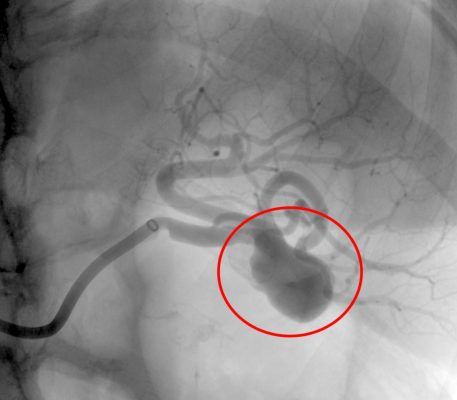

30/06/2025 – Aulas e Palestras Ministradas - Pseudoaneurisma Gigante de Ilíaca Externa

06/08/2024 – Relato de Casos